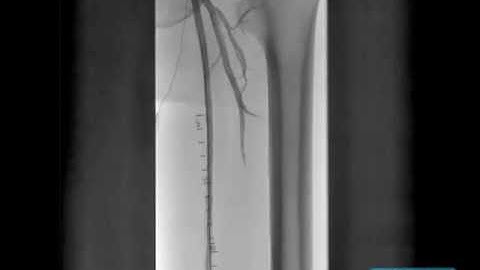

Mid SFA CTO Treated with Cross Boss #1